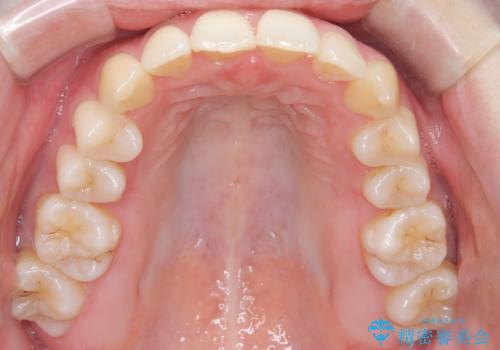

【インビザライン】 前歯の反対咬合を治したい

左下5番は先天性欠損のため乳歯は抜歯しインプラントにて欠損補綴しています。